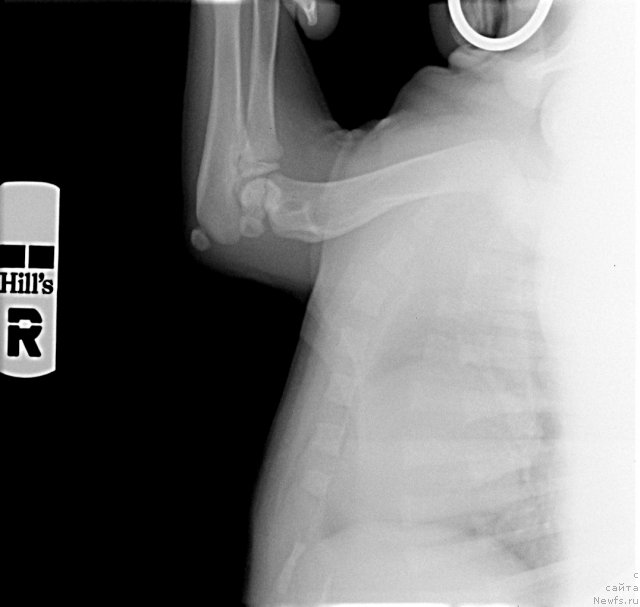

Посмотрите на суставы 2-х месячного щенка лабрадора. Насколько большие ростовые зоны. Какие огромные расстояния между костями суставов. И насколько еще не сформированны суставы. Особенно локтевые. А это собака гораздо легче ньюфаундленда. На него просто наступила сука. И такие травмы.

Фотография № 116289

Фотография № 116290

Фотография № 116291

А это рентген суставов месячного щенка.

Фотография № 116297